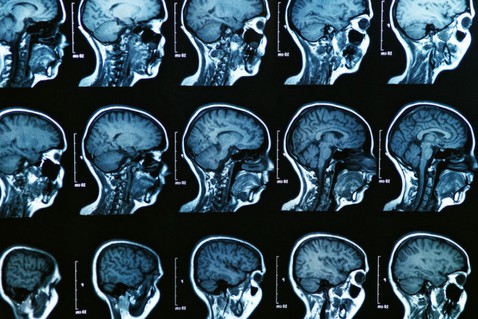

Магнитно-резонансная томография головного мозга (МРТ) — один из способов определения изменений в головном мозге, которые характерны для болезни Альцгеймера.

В некоторых случаях врач назначает магнитно-резонансную томографию головного мозга (МРТ) — это в первую очередь нужно для того, чтобы проверить, не является ли деменция (или приобретенное слабоумие) следствием инсульта, поражения сосудов и гидроцефалии. Кроме того, при МРТ оценивается состояние нервных волокон и развитие атрофии особого отдела головного мозга — гиппокампа (он является у человека центром памяти и эмоций).